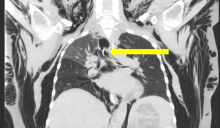

Figure 1: An open tracheostomy was performed and through this a long 6.0 armored endotracheal tube was placed in the left mainstem bronchus. A long, pediatric 5.0 endotracheal tube was placed into the right mainstem bronchus orally.